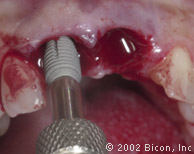

Установка двух 5.0mm x 8.0mm HA имплантантов Bicon

Определение направления оси и глубины шахты имплантантов

Abutment Shoulder Gauge

Вид после установки